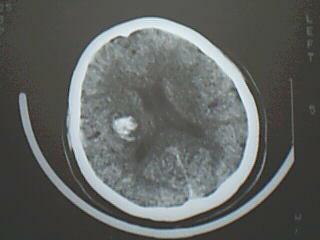

以下是引用黑白光影在2008-8-14 21:33:00的发言:[br]支持右侧基底节区脑出血。

以下是引用liyf在2008-8-14 20:00:00的发言:[br]右侧基底节区脑出血。